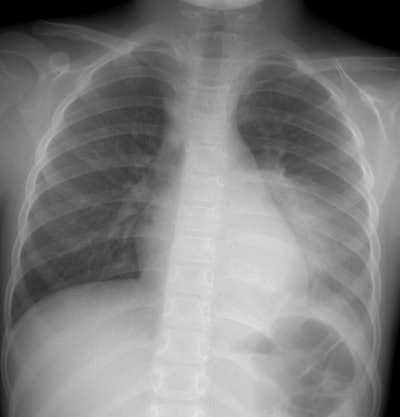

The CXR demonstrates a large left lung mass. The patient was initially felt to have a pneumonia, but subtle rib destruction can be seen involving the left posterior ninth rib. When the radiographic findings did not improve a CT scan was performed (See below). (Click images to enlarge)